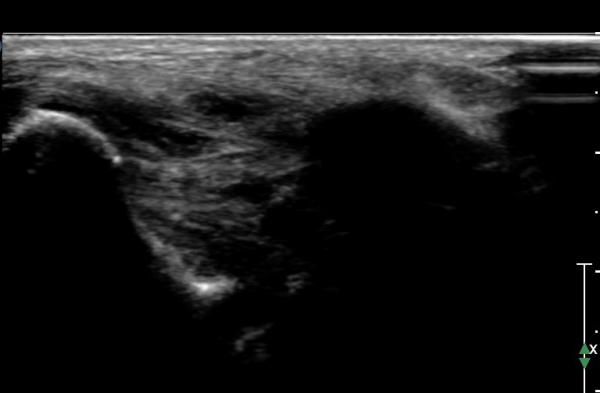

ÃÊÀ½ÆÄ °Ë»ç :  ¹ß¸ñ ¾ÕÂÊ Á¾´Ü¸é°Ë»ç¿¡¼­ ƯÀÌ ¼Ò°ß º¸ÀÌÁö ¾Ê´Â´Ù(»çÁø 1)